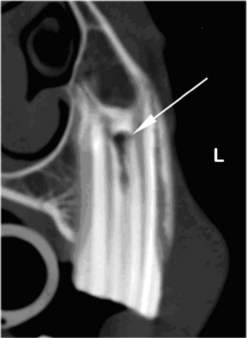

image image

Fig. 13.38 (A & B) Malformed and malerupting 302 with retained deciduous 702. The malerupting 302 has an abnormal (reversed) rostral curvature in the lateral view (arrow) (B). 703 is present lateral to 702, but 303 does not appear to have developed.

(Radiographs courtesy of B. Chilvers.)